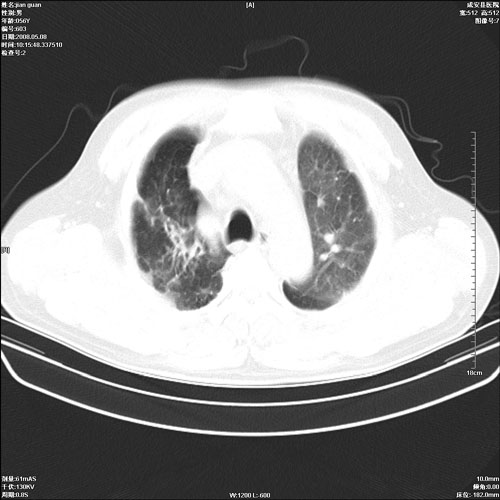

病人 男 60岁 主诉 胸闷 无明显发热 一般情况尚可。

两上肺陈旧性结核;慢支肺气肿、伴感染?

1.右上肺陈旧性肺结核.

两上肺陈旧性结核;慢支肺气肿

1.两上肺陈旧性结核;慢支肺气肿。

考虑.两上肺陈旧性结核;慢支肺气肿。肺心病

两上肺陈旧性结核,慢支肺气肿。

两上肺陈旧性结核;慢支肺气肿。肺肺间质纤维化

两上肺陈旧性结核;慢支肺气肿。

1.陈旧肺结核;

2.慢支肺气肿;

3.肺心病.